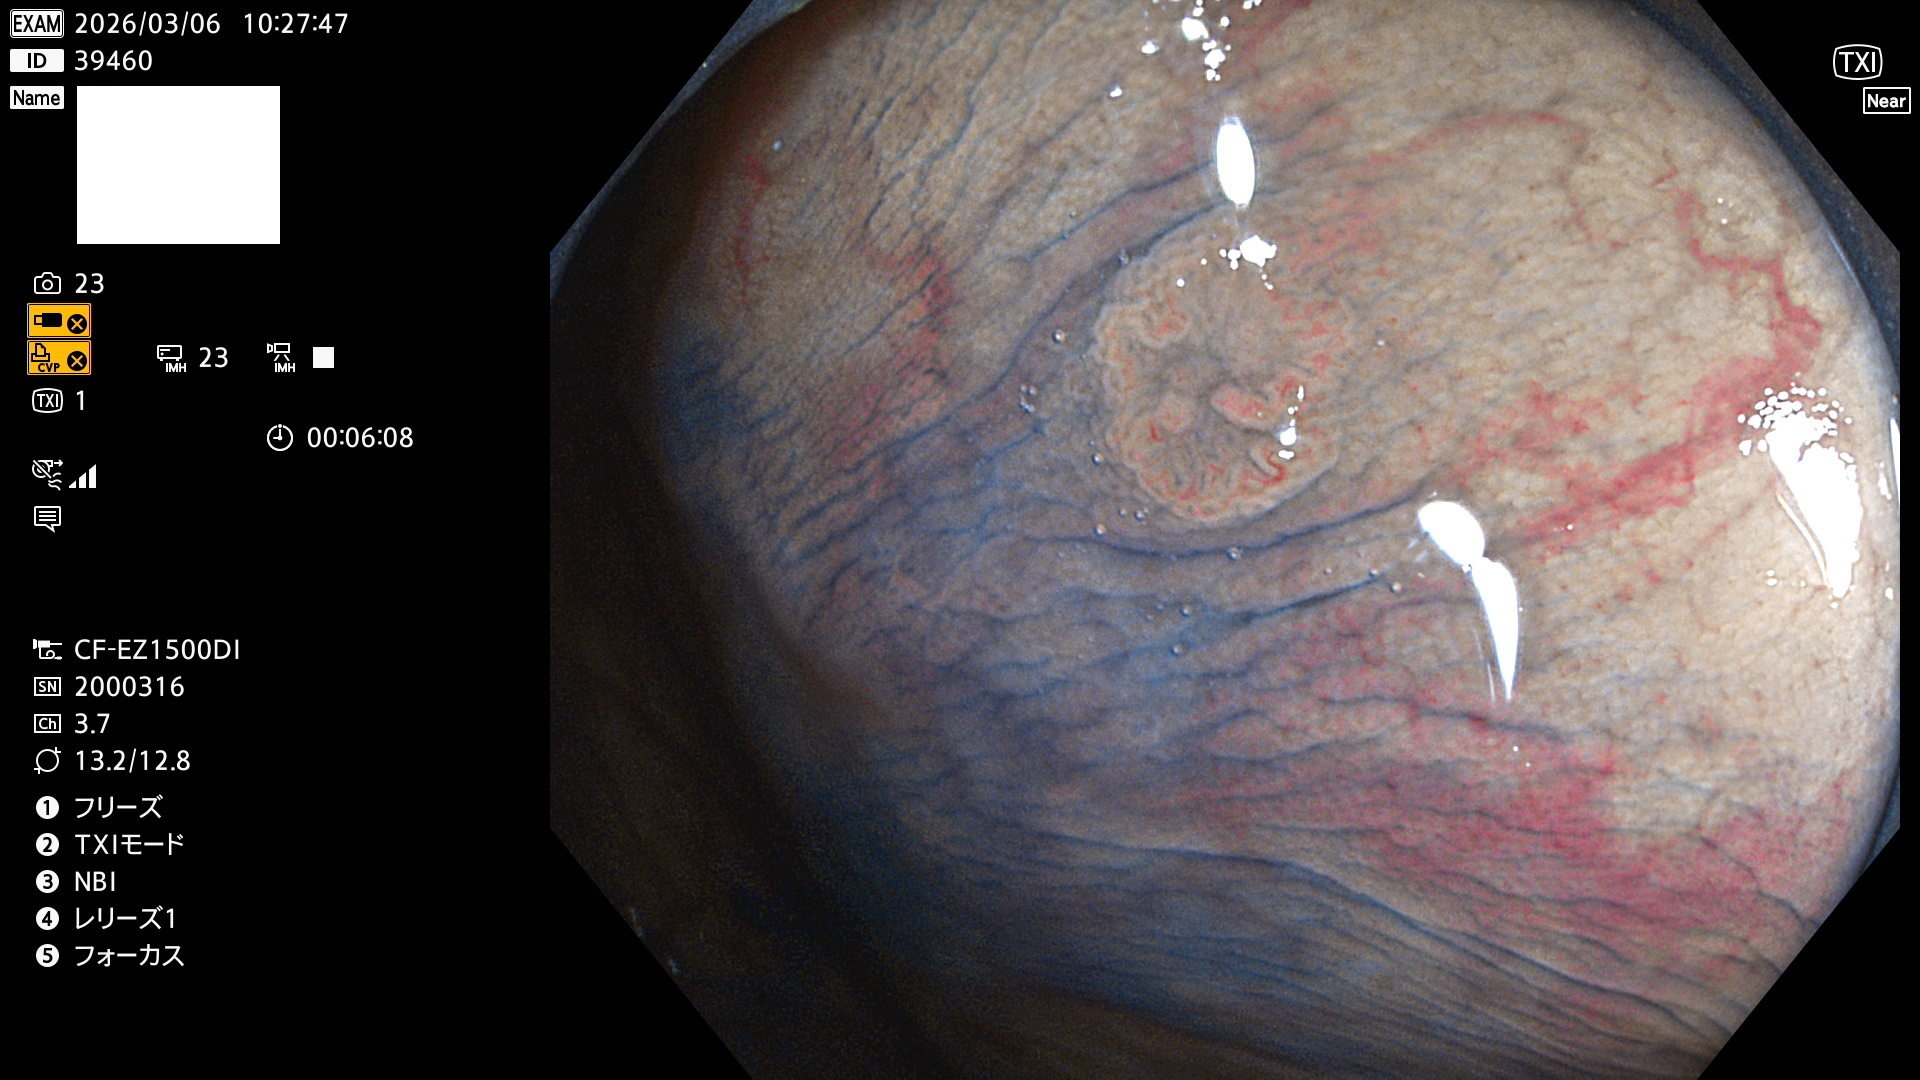

完全に平坦な物をUb、陥凹している物をUcと呼びます。Ubは認識が困難で、Ucはびらん(炎症)と紛らわしいために見落とされやすく、「内視鏡後・大腸癌」の原因になります。

専門的)Uc=De Novo癌? 内視鏡の解像度が低かった時代、このような説もありました。しかし今日の高精度内視鏡では良性の微小なUc型腺腫(APC遺伝子異常の腺腫)が日常的に見つかります。Ucこそが多段階発癌(Adenoma-Carcinoma Sequence)のMain Routeです。

毎週の検査(木・金・土・日)に発見されたUbとUc型・腺腫を、その週の日曜の夜にUPし1週間、提示します。

2026年3月5日〜3月8日の4日間(40件)9個 (Uc_ADR=9個/40人=23%)